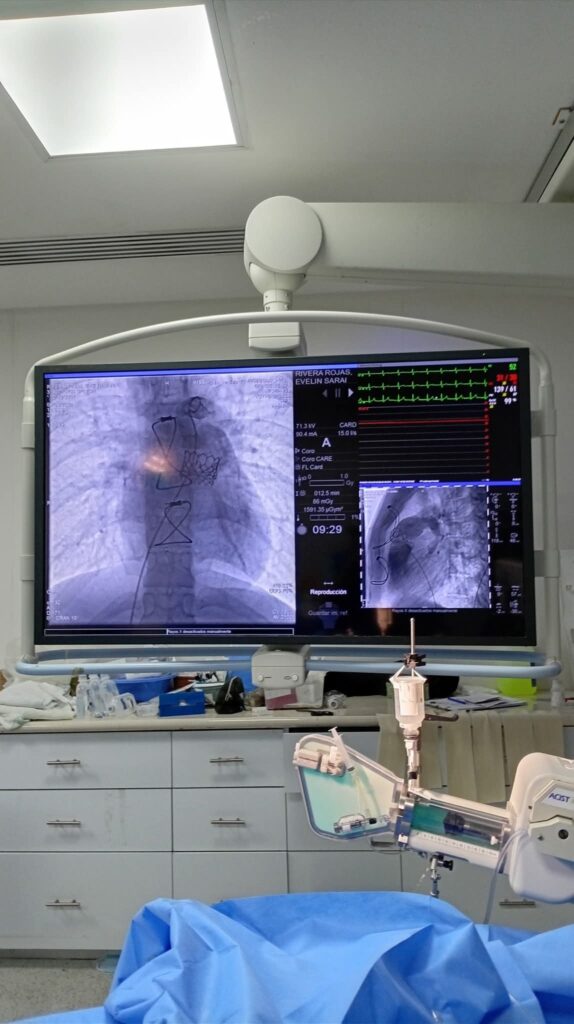

Coahuila de Zaragoza, 23 de abril de 2026.- El Instituto Mexicano del Seguro Social (IMSS) marcó un avance significativo en la atención médica en Coahuila al sustituir la tradicional cirugía a corazón abierto por un procedimiento mínimamente invasivo para corregir defectos cardíacos congénitos. Este logro se concretó en el Hospital General de Zona No. 71, donde especialistas implementaron esta técnica con resultados exitosos.

De acuerdo con información institucional del IMSS, dos jóvenes diagnosticados con Tetralogía de Fallot fueron intervenidos mediante este método, lo que les permitió una recuperación más rápida y una notable mejora en su calidad de vida. A diferencia de la cirugía convencional, esta alternativa reduce riesgos, tiempos de hospitalización y complicaciones postoperatorias.

Con esta innovación, el Hospital 71 se posiciona como pionero en el norte del país en la aplicación de este tipo de procedimientos, consolidando al IMSS como una institución que apuesta por la modernización médica y el uso de tecnología de vanguardia para salvar vidas.